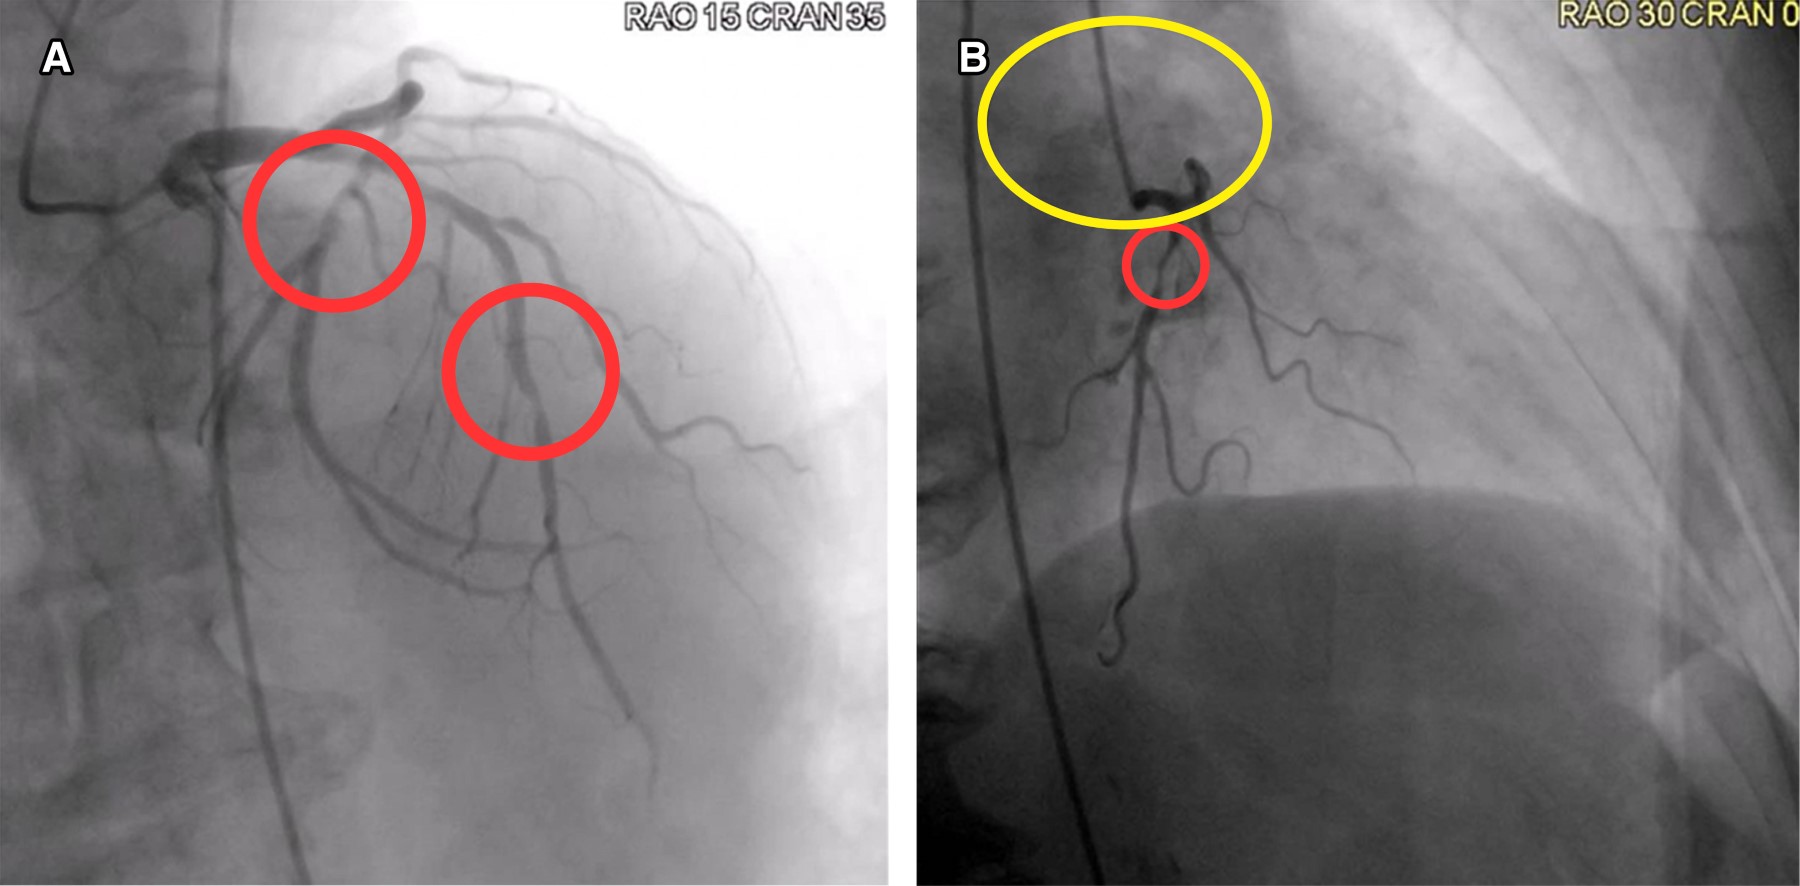

Figura 2